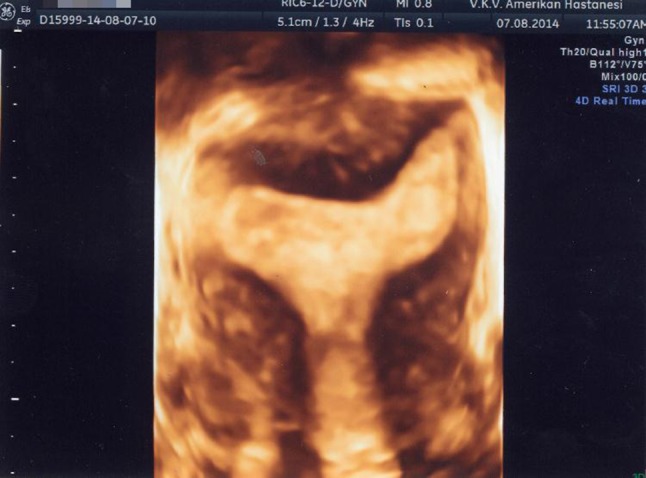

تصویر سه بعدی از رحم جدا شده. نمای تاجی به وضوح کانتور خارجی طبیعی رحم و قسمت انتهایی عمیق حفره را به تصویر می کشد.